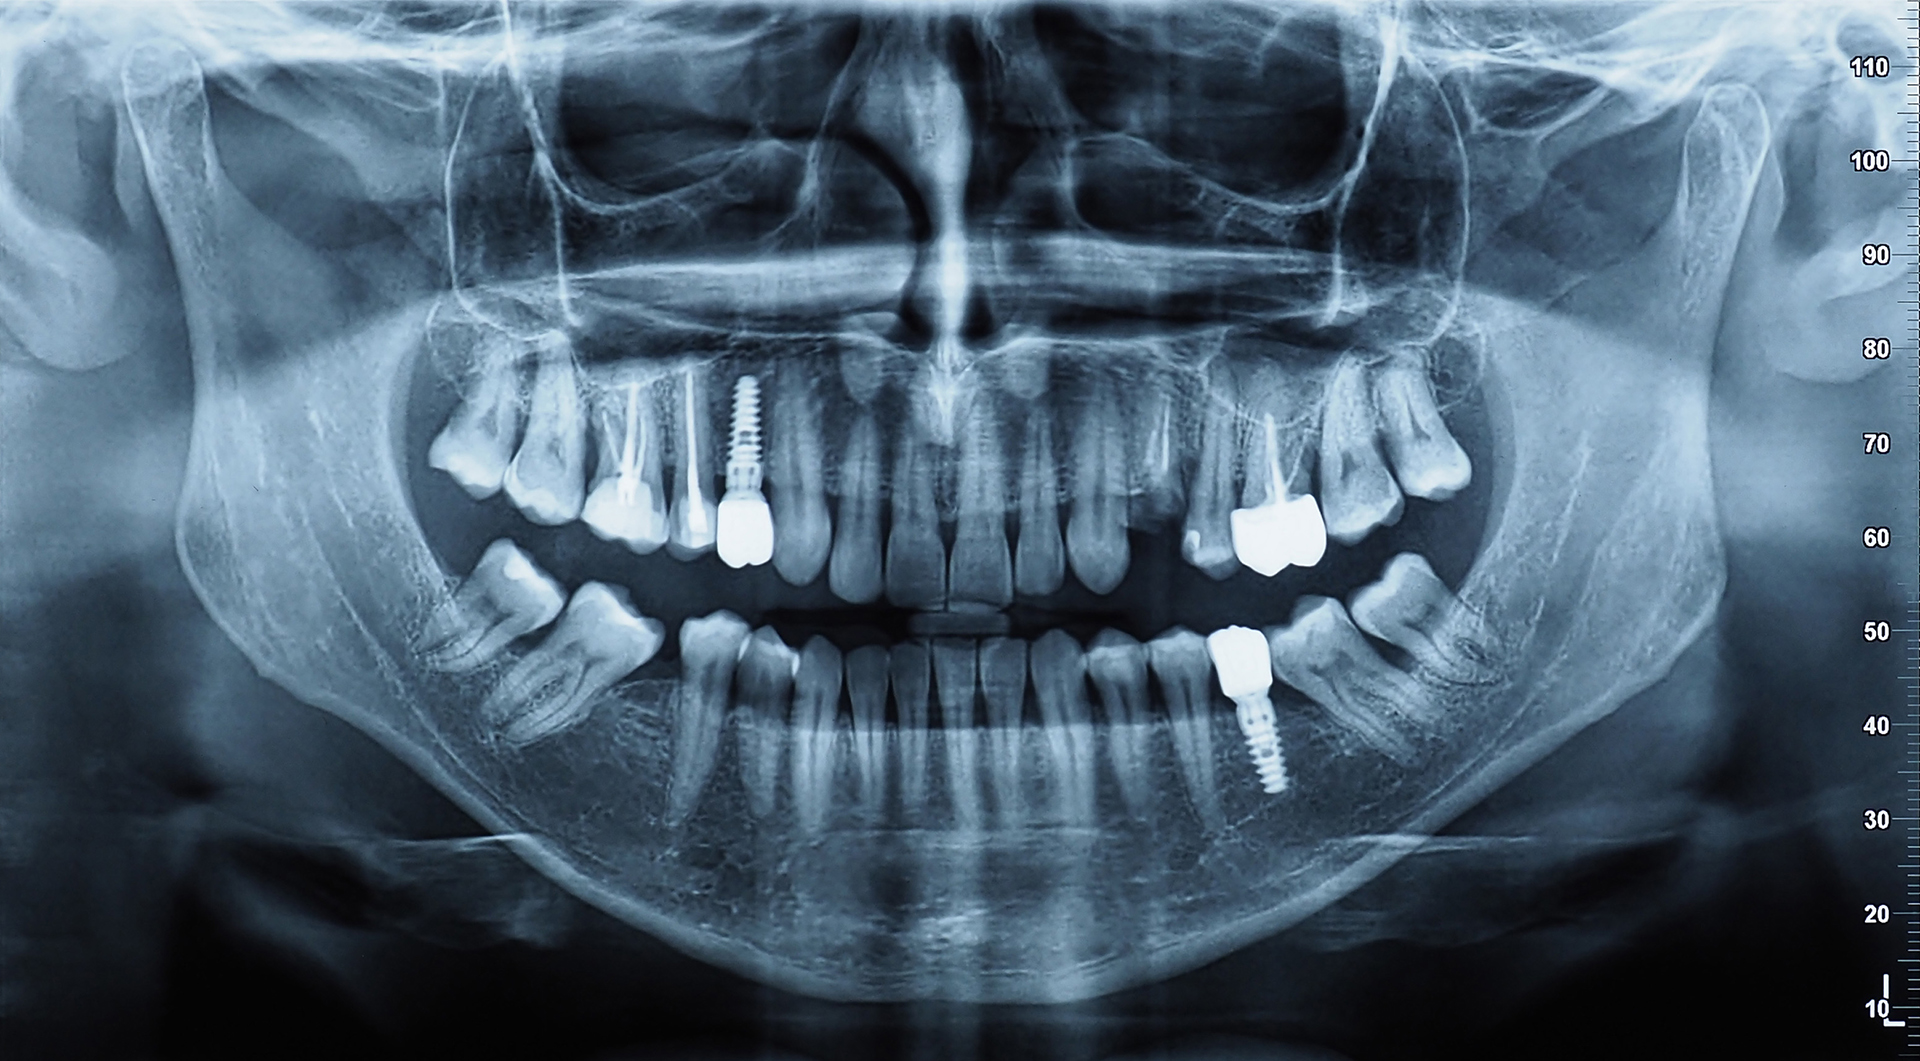

- Implant Fixture – The titanium (or zirconia) post surgically inserted into the jawbone.

- Abutment – The connector that joins the implant to the crown.

- Crown – The visible, custom-crafted porcelain tooth that mimics your natural teeth.

- Bone grafting or sinus lift for patients with insufficient bone volume

- 3D imaging and diagnostics to ensure accurate implant placement

- Consultation & Planning – X-rays, scans, and treatment planning

- Surgical Implant Placement – Under local anaesthetic, the implant is inserted into the jaw

- Healing & Osseointegration – 3–6 months for bone to fuse around the implant

- Abutment & Crown Placement – The final phase completes your smile

- Digital impressions and 3D-guided placement for precision